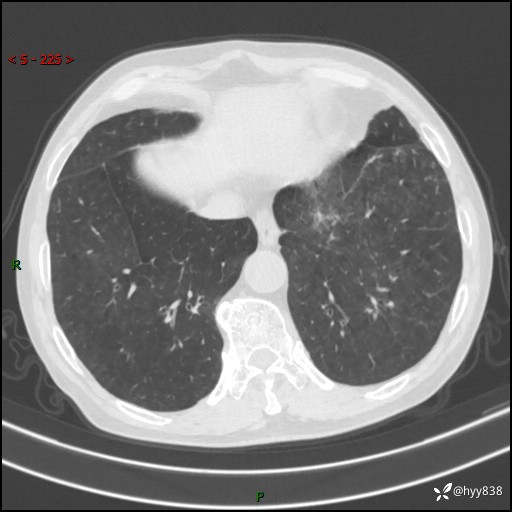

儿女怕老人寂寞,养了两只鹦鹉,呼吸科主任问我典不典型---结果公布~

武医生 等 4 位达人已点赞患者性别:男

患者年龄:71岁

主诉:喘气半年余,咳嗽乏力伴味觉减退2月余

简要病史:者半年前左右无明显诱因出现呼吸困难,轻微运动后出现喘气,未予以重视。2月余前受凉感冒后出现咳嗽,咳白色泡沫痰,不易咳出,于当地医院行输液治疗,未见明显好转,并感觉全身乏力,体力下降,并感口苦,味觉减退。近10余天前感咳嗽喘气加重,咳白色泡沫痰,不易咳出,口苦,味觉减退加重。为进一步检查及治疗,入我院就诊,门诊以“呼吸困难”收入院治疗。 起病以来,患者精神,睡眠,饮食欠佳,大小便可,体力下降明显,体重稍下降。

辅助检查:CT

临床诊断:呼吸困难

胸部CT平扫